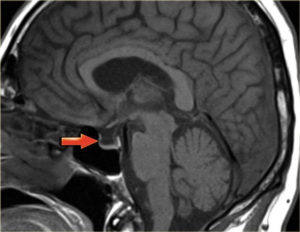

- Еще одно показание — синдром пустого турецкого седла.

- Пустое турецкое седло. По внутренней поверхности турецкого седла «распластан» гипофиз. Его покрытие (диафрагма) при этом провисает в полость. Гипофизарная ткань становится похожа на тонкий полумесяц толщиной 2 мм.

По внутренней поверхности турецкого седла «распластан» гипофиз. Его покрытие (диафрагма) при этом провисает в полость. Гипофизарная ткань становится похожа на тонкий полумесяц толщиной 2 мм. Встречается после родов, абортов, лучевой терапии.